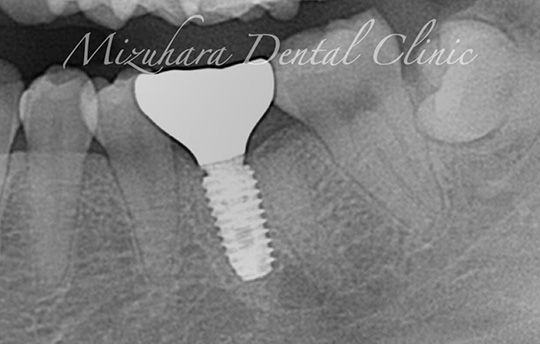

豊富な臨床経験に基づくインプラント治療

インプラント治療

米インディアナ大学歯学部 インプラント科のプログラムを受講し、国際的な教育環境のもとで臨床経験を積んだ当院長によるインプラント治療。